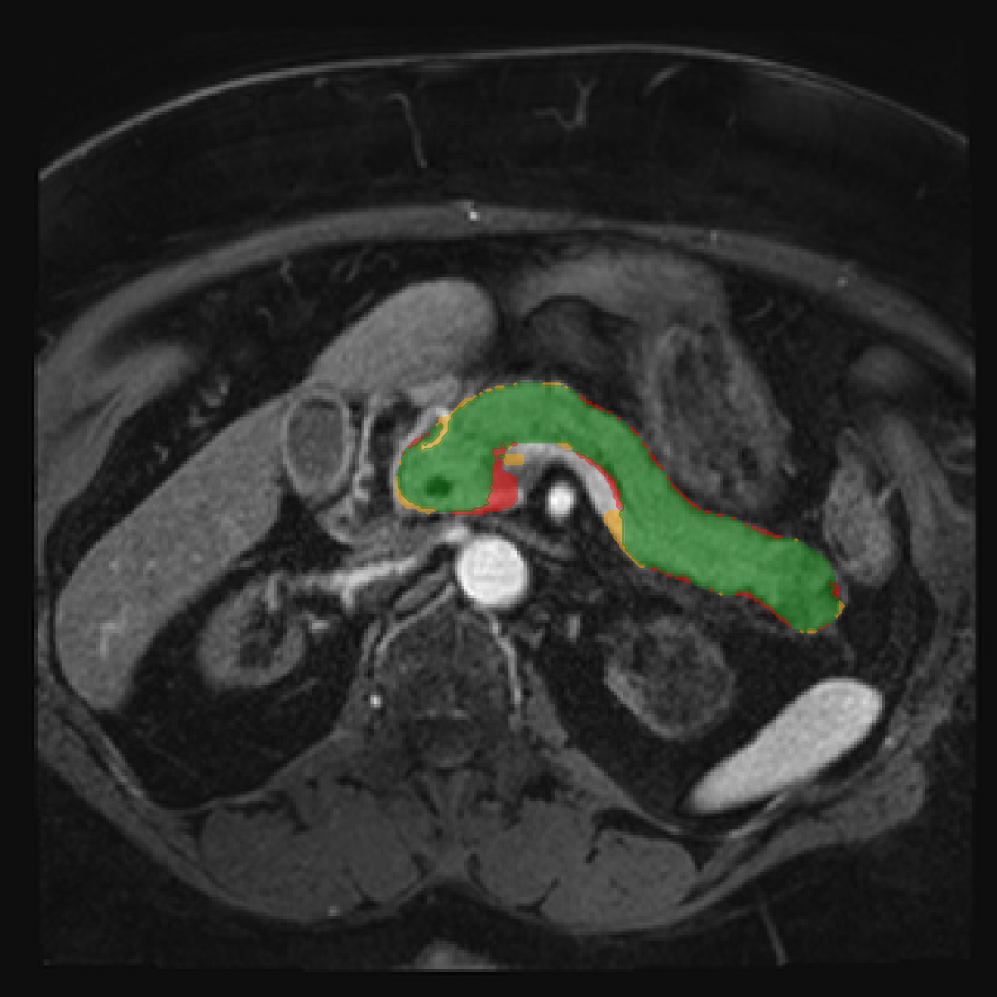

Accurate pancreas segmentation is a critical prerequisite for precise cyst analysis and classification. Recently, we developed PanSegNet [zhang2025large], a novel segmentation architecture incorporating linear self-attention layers [zhang2022dynamic] within the nnUNet framework [isensee2021nnu] to enhance global information modeling capabilities while maintaining computational efficiency (Fig. 1). PanSegNet demonstrated exceptional segmentation performance across both T1W and T2W modalities, achieving mean dice scores of 86.817.30% and 89.626.38%, respectively (Table 1, Fig. 2b-c). This performance significantly exceeded that of Swin-UNETR [hatamizadeh2021swin], one of the most used state-of-the-art transformer-based medical segmentation models, which achieved dice scores of 79.091.40% and 76.290.66% for T1W and T2W, respectively (). In this study, we integrated PanSegNet into our Cyst-X engine along with a classifier for risk prediction. In Section 2.2, we show that the choice of segmentation model affects the classification results. The performance advantage of PanSegNet was consistent across all seven medical centers, demonstrating robust generalization despite variations in imaging protocols and equipment (Table 1). This cross-institutional reliability is particularly important for clinical applications, where model performance must remain consistent regardless of imaging site or acquisition parameters.

Each patient was categorized into one of these three ground truth classes: no risk/control, IPMN low-risk, or IPMN high-risk. To evaluate variability in image acquisition, we applied uniform manifold approximation and projection (UMAP) to image quality indicators, revealing distinct clustering patterns by imaging center and slice thickness. This heterogeneity reflects real-world clinical variability, enhancing the dataset’s generalizability while presenting technical challenges for model development. Fig. 6 shows examples of low-grade, high-grade, and cancer developing IPMNs from the Cyst-X dataset.